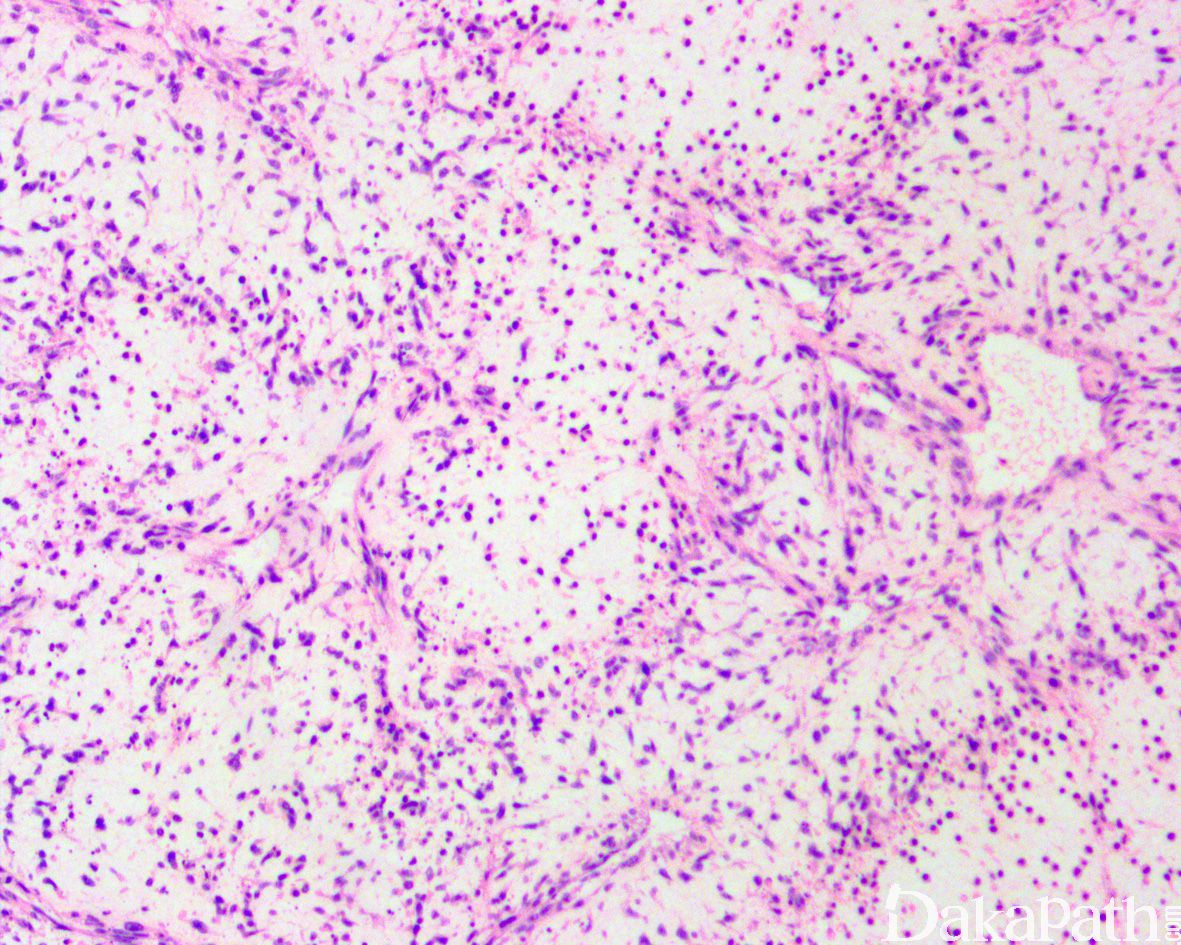

部分病例可见局灶的间质黏液变性,黏液区瘤细胞缺乏席纹状结构,瘤细胞呈星芒状,间质微血管网增生明显;

黏液纤维肉瘤:黏液变异型 DFSP 需要与黏液纤维肉瘤区别;黏液纤维肉瘤瘤细胞的异型性更明显,常见血管周围聚集和假脂肪母细胞

黏液脂肪肉瘤:粘液变异型 DFSP 亦需要与黏液性脂肪肉瘤区别;黏液脂肪肉瘤多位于皮下或肌内,罕见累及真皮,病变内可见复杂的鸡爪样血管网,瘤细胞呈卵圆形,可见单泡或多泡状脂肪母细胞,免疫组化染色表达 S100 蛋白;